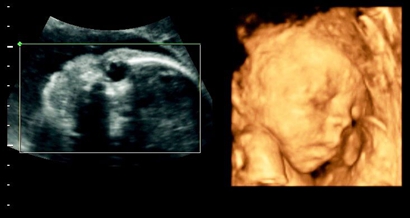

四维彩超最后结果出现问题也是有概率的,四维彩超虽然准确率十分高,但是在做检查的时候,难免会出现宝宝姿势不对,或者是胎儿的手部遮挡了生殖器的现象,导致医生的判断出错,当医生正在操作B超的时分,若宝宝正处于背部的姿态或手脚正好蜷到一同,从而遮挡了性别器官,这也会形成性别的改动,另外假如你家宝宝太调皮了,不太配合,姿态不对,医生也不可以很精确的看到Ta的生殖器,结果就没有那么精确了。

四维一般都是二十四周以后照的,这么大的孕周出错的机会还是比较小的,虽然不是百分之百准确的,但是出错的概率还是会比较少的,大部分情况都是不会出现翻盘的情况,四维超声同其它超声检查相比,可以实时观察人体内部器官的动态运动,也能准确地分辨出胎儿的性别。虽然四维彩超能够看清胎儿的性别,但在检查过程中,为了避免透露胎儿的性别,医生会主动的回避胎儿的性别特征以及下半身,因此最好找熟人的医生做这样才能更准确知道宝宝的性别。